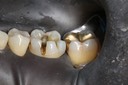

Gary Umeda #18, 19, 20 finish